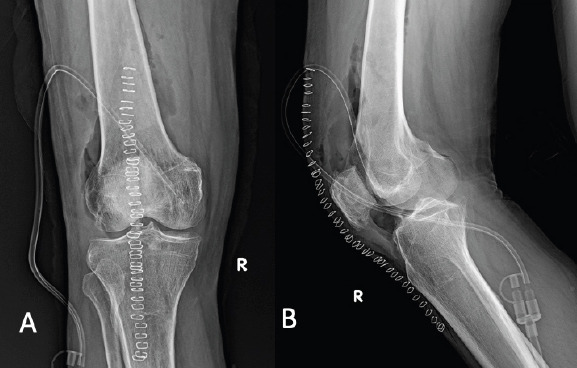

Case report: A 65-year-old male patient presented to the hospital with sudden inability to bear weight on his right lower limb, inability to flex the knee, which was associated with swelling of the knee, and the limb was externally rotated for 3 days. A fracture of the right neck of the femur was identified on X-ray of the pelvis with bilateral hips. There was no history of trauma. He is a known case of chronic kidney disease for 3 years and is also a known hypertensive and type 2 diabetes mellitus for 15 years, and is currently undergoing dialysis thrice per week. The affected knee was aspirated and was found to have S. marcescens infection, localized there itself; blood culture and intraoperative hip aspirate were negative for the same organism. He underwent right knee arthrotomy with synovectomy and was started on IV antibiotics based on the culture and sensitivity report.